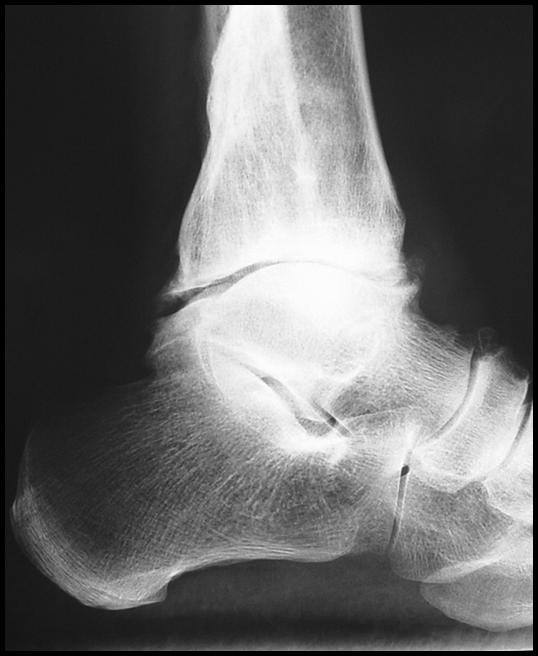

Перелом – это достаточно распространенный вид травмы голеностопного сустава, на долю которого приходится около 15% от общего числа механических повреждений костно-суставных сегментов опорно-двигательного аппарата. Происходит опосредованное воздействие травмирующей силы, то есть при жестком фиксировании задней части стопы ее передний отдел продолжает движение. Травма (перелом) голеностопа возможна при падении с высоты, в результате неудачного приземления при выполнении физических упражнений, катании на лыжах, коньках. При получении травмы дальнейшее перемещение или движение человека становится весьма ограничено, так как голеностопный сустав болит. Что делать?

Не следует производить пораженной нижней конечностью какие-либо физические действия. Человеку нужна помощь медицинского работника и абсолютный покой, так как характер повреждения можно определить лишь при рентгенологическом исследовании. Нужно немедленно доставить пациента в ближайшее медицинское учреждение или вызвать Скорую помощь.